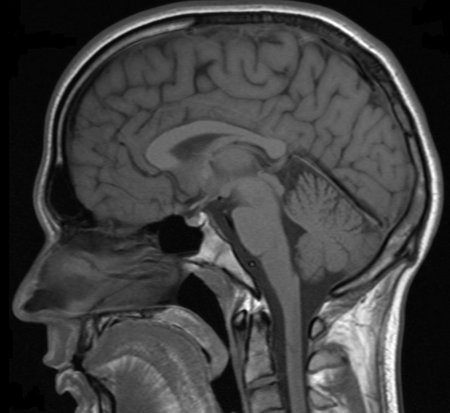

Millions of MRI, or magnetic resonance imaging, scans are performed each year to diagnose health conditions and perform biomedical research. The different tissues in our bodies react to magnetic fields in varied ways, allowing images of our anatomy to be generated. But there are limits to the resolution of these images—generally, doctors can see details of organs as small as a half millimeter in size but not much smaller. Based on what the doctors see, they try to infer what is happening to cells in the tissue.

Mikhail Shapiro, assistant professor of chemical engineering, wants to make a connection between MRI images and what happens in tissues at scales as small as a single micrometer—that's about 500 times smaller than what's possible now.

"When you look at a splotchy MRI picture, you may want to know what's happening in a certain dark spot," says Shapiro, who is also a Schlinger Scholar and Heritage Medical Research Institute Investigator. "Right now, it is hard to say what's going on at scales smaller than about half a millimeter."

In a recent study published in the journal Nature Communications, Shapiro and his colleagues introduced a method to correlate magnetic field patterns in tissue, which occur on micrometer scales, with the larger, millimeter-scale features of MRI images. Ultimately, the method would allow doctors to interpret MRI pictures and better diagnose various conditions.